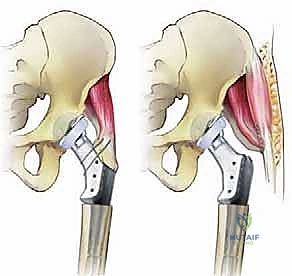

الفواصل والارتباطات العضلية: مسارات الجراحة وإعادة البناء

لا يقتصر نجاح الجراحة على العظم والمعدن فقط، بل يعتمد بشكل حاسم على العضلات والأنسجة الرخوة التي تحرك هذا المفصل وتحافظ على استقراره.

- آلية العضلات المبعدة (Abductor Mechanism): ترتبط هذه العضلات بالمدور الكبير (Greater Trochanter). في حالات فقدان العظم الشديد، غالباً ما يكون المدور الكبير مكسوراً، أو ممتصاً، أو مفقوداً تماماً. يمثل إعادة ربط هذه العضلات بالطرف الاصطناعي المعدني تحدياً جراحياً هائلاً. يستخدم الأستاذ الدكتور محمد هطيف تقنيات خياطة متقدمة وتطعيم عظمي لضمان التصاق العضلات بالمفصل الجديد، وهو ما يمنع خلع المفصل بعد الجراحة.

6. إعادة بناء الأنسجة الرخوة (Soft Tissue Reconstruction)

المفصل المعدني وحده لا يكفي؛ يجب أن يكون مستقراً. يقوم الدكتور هطيف بإعادة ربط العضلات المبعدة (Abductors) بالمفصل الجديد. تحتوي المفاصل الحديثة على ثقوب خاصة (Suture holes) لتمرير خيوط قوية جداً لربط العضلات والأوتار بالهيكل المعدني. كما يتم تغطية المفصل المعدني بالأنسجة المحيطة (مثل عضلة Vastus Lateralis) لتقليل خطر العدوى.